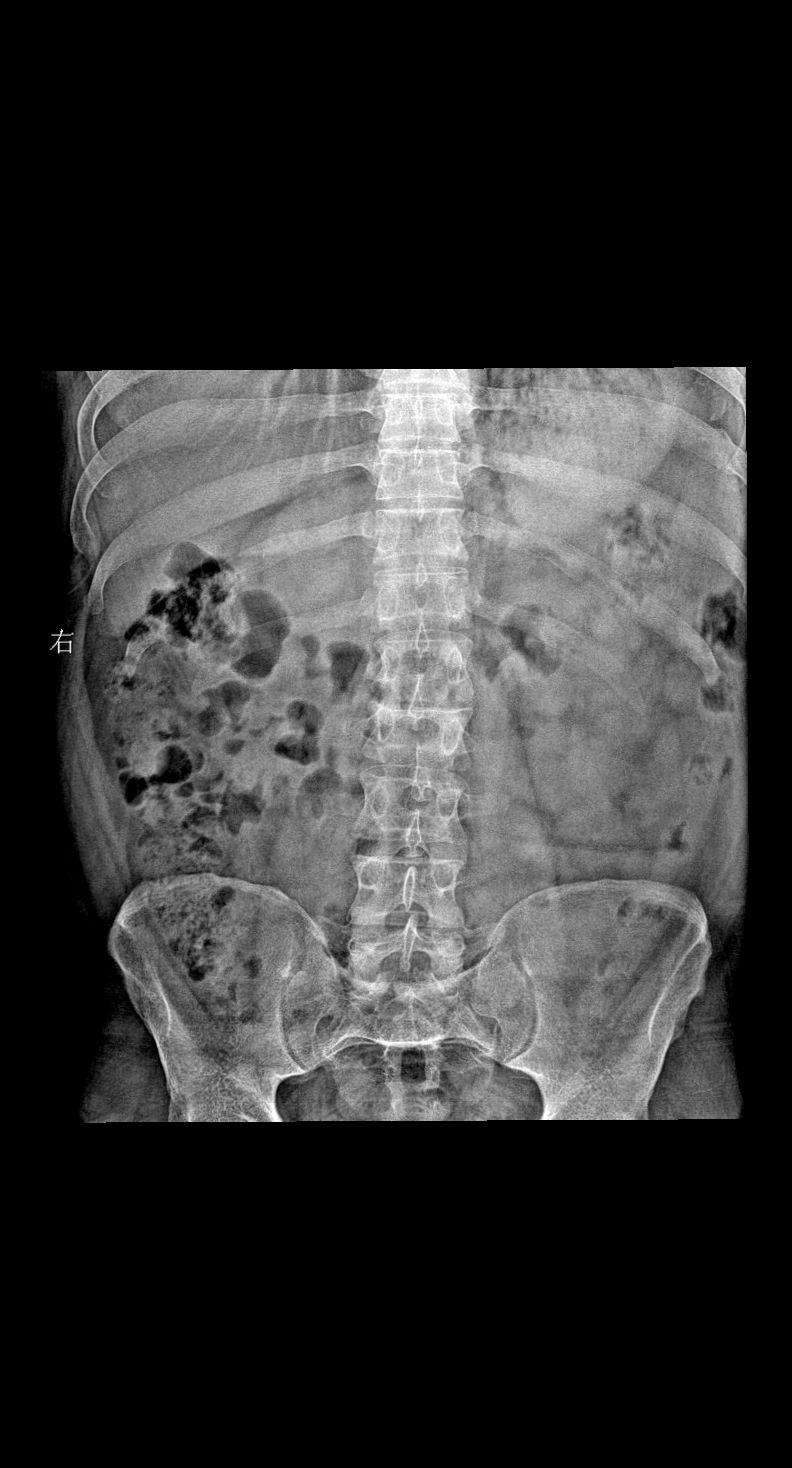

男 36岁 外伤 腰椎正侧位